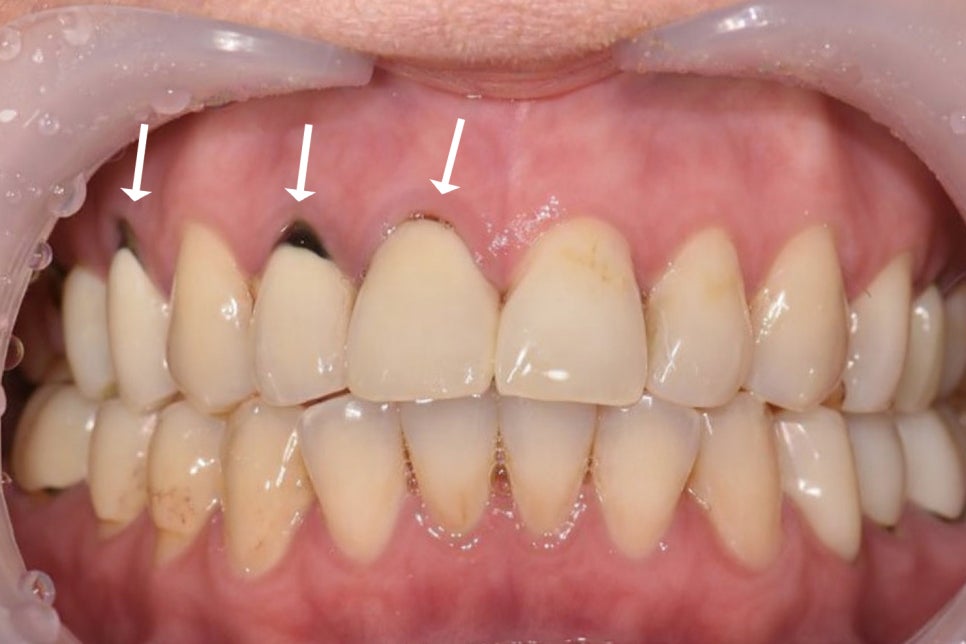

시간이 흐르면서 보철과 자연치가 맞닿는

경계 부위에 틈이 벌어지면

이 틈을 통해 세균이나 음식 찌꺼기,

타액이 반복적으로 스며들 수 있고

그 결과 크라운 아래에서

우식이 다시 시작될 수 있습니다.

겉으로 잘 드러나지 않을 때가 있기 때문에

환자 스스로 인지하기 어렵다는 특징이 있으며

초기에는 통증 또한 거의 없기 때문에

정기 검진을 통해서만 발견할 수 있습니다.

특히 크라운을 씌운 곳은

보철을 제거하기 전까지

정확한 상태를 확인하기 어려우며

이미 근관이 충전되어 있다면

잇몸에 염증이 생기면서

알게 될 때가 많습니다.